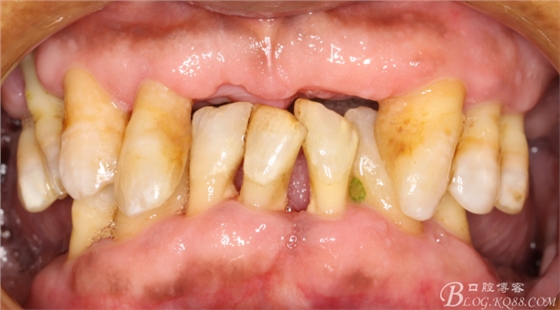

3:拔除其他松動(dòng)牙

經(jīng)過系統(tǒng)的治療,患者的牙周狀況得到明顯的改善,改變冠根比例之后的基牙沒有明顯的松動(dòng),

考慮治療方案:

上頜基牙比較分散,選擇 5顆基牙的套筒冠修復(fù),

下頜由于44治療之后,松動(dòng)度改善不大,原來的咬合創(chuàng)傷比較大,不能承擔(dān)較大的(牙合)力,選擇覆蓋義齒,把它磨短平齊牙齦,

其他牙比較集中,選擇雙端球帽式附著體修復(fù)雙端游離缺失